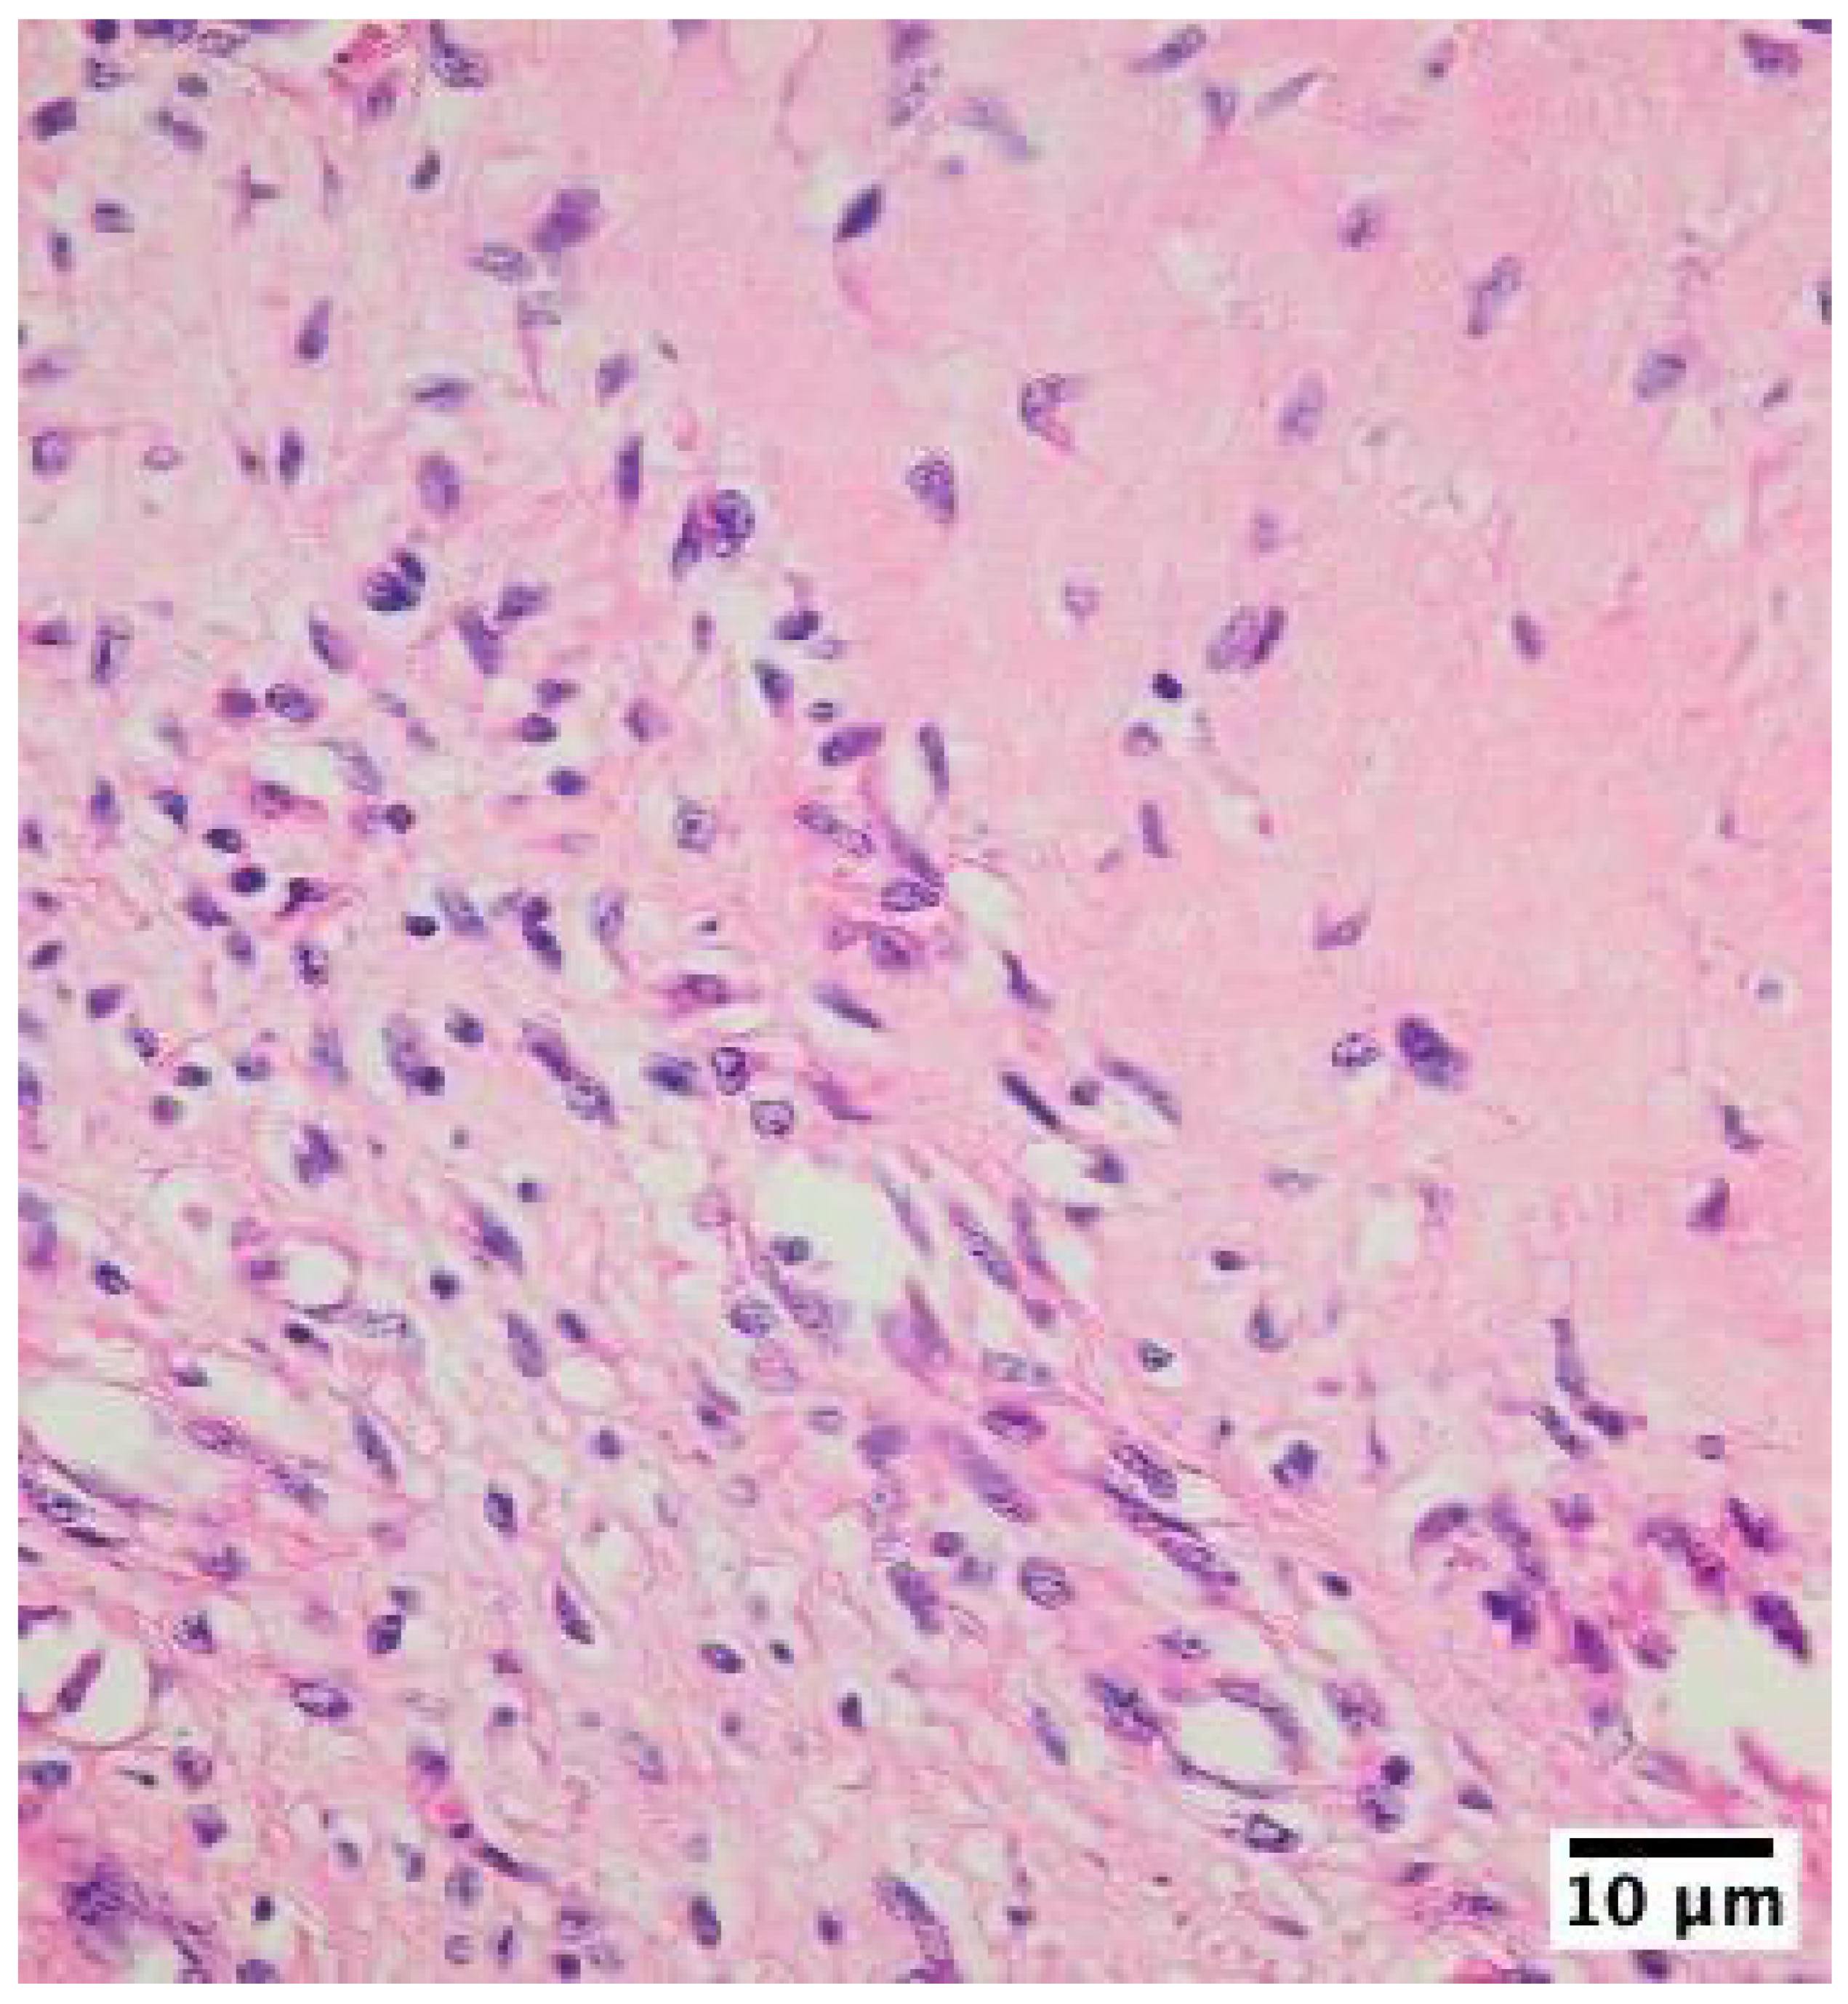

The inflammatory infiltrates in non-IE cases consisted mainly of macrophages and lymphocytes, suggesting a chronic inflammatory process rather than an acute infection (Figure 2, Figure 3, Figure 4).

Figure 4. Histological examination of mechanical heart valve tissue specimen in mitral position with non-infective inflammatory degenerative lesions showing inflammatory infiltrates with lymphocytes and macrophages cells as visualized using hematoxylin-eosin-saffron staining at 400x magnification with an Olympus BX43 microscope and XC30 camera. .